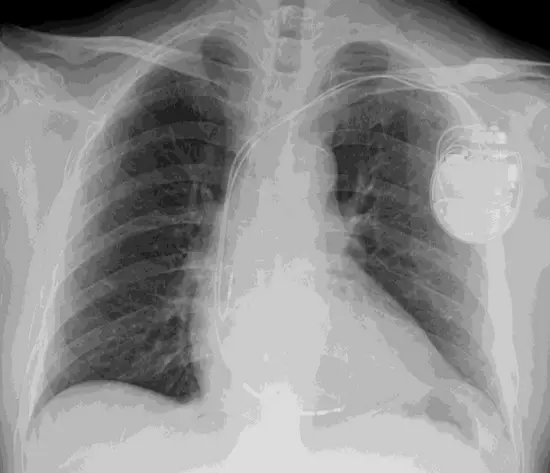

- 裝置識別:X 光影像顯示患者左側鎖骨下方(Left Infraclavicular area)植入有一具金屬外殼的電子裝置,且有導線(Leads)經由靜脈延伸至心臟腔室(右心房與右心室),可判斷為心臟節律器(Pacemaker)或植入式去顫器(ICD)。

- 手術切口暗示:裝置位於左胸皮下或胸肌下,未見胸骨鋼絲(Sternal wires),這排除了正中胸骨切開術(Median Sternotomy)的可能性。

- 解剖關聯:由於裝置與導線位於左側,術後患側(左側)上肢的活動限制是關鍵。